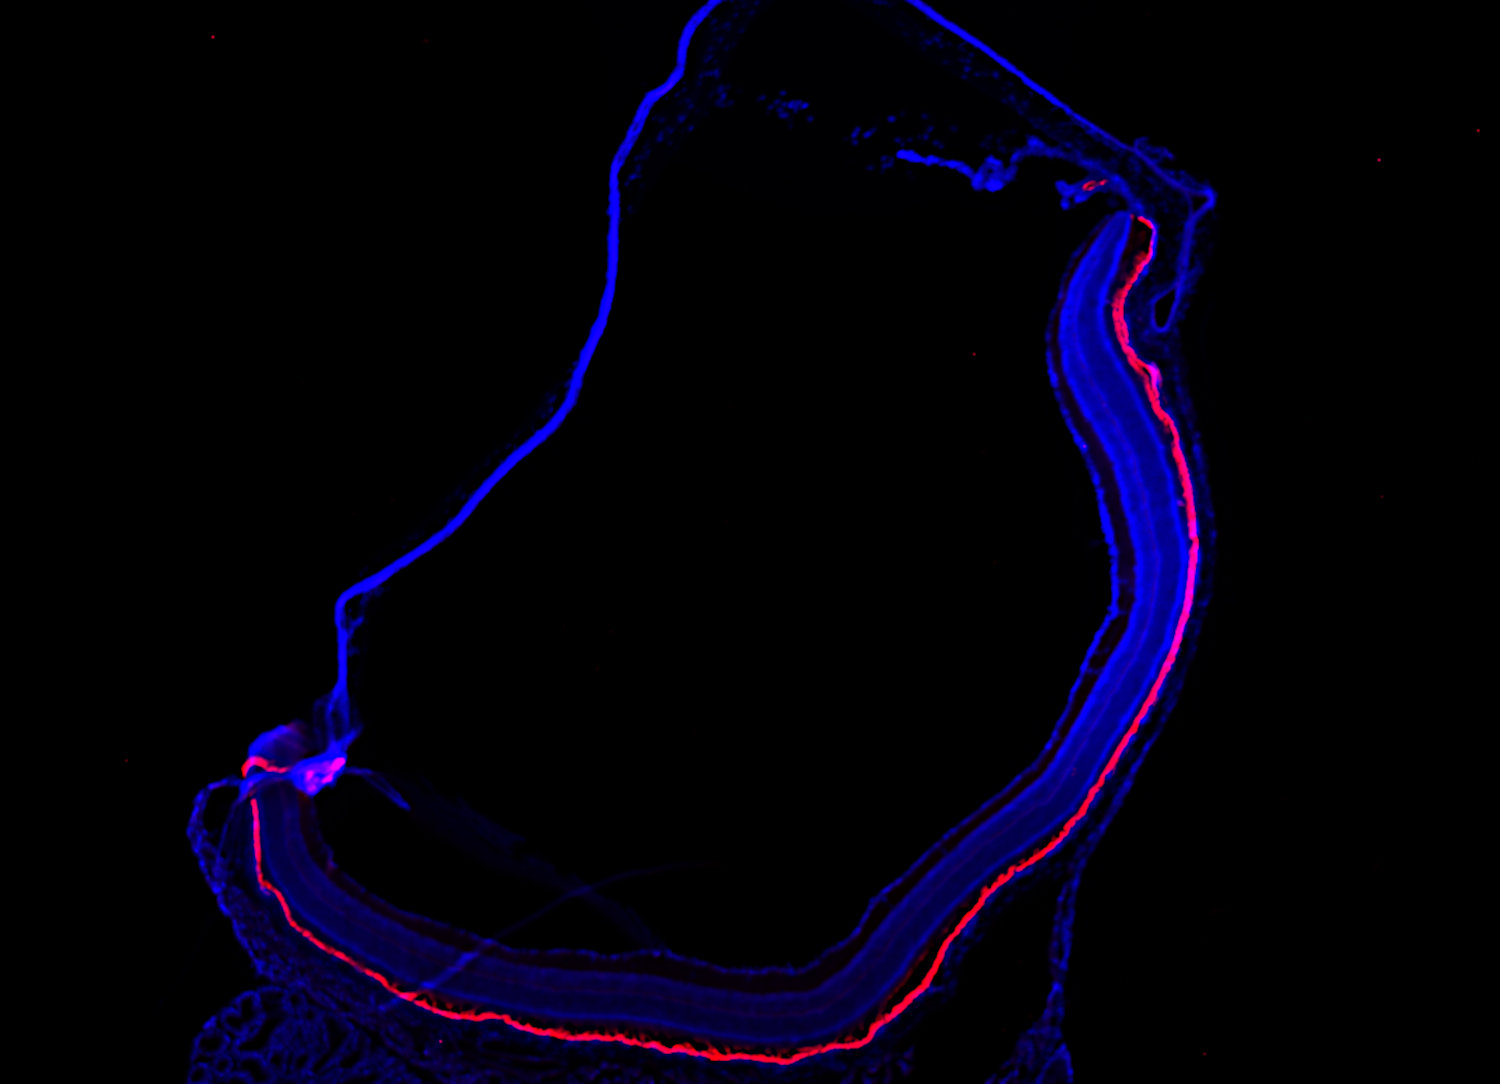

Monocarboxylate transporter3 (red) and Parvalbumin (green) staining of mouse retina.

Monocarboxylate Transporter3 (MCT3), encoded by Slc16a8, is a proton-coupled lactate transporter localized to the basolateral membrane of the retinal pigment epithelium (RPE), where it facilitates lactate and proton efflux to the choroid. Its expression is highly tissue-specific, mainly restricted to the RPE and choroid plexus epithelium. (1,2) MCT3-deficient mice (Mct3⁻/⁻) exhibit reduced scotopic electroretinogram (ERG) amplitudes despite intact retinal morphology and healthy photoreceptors, suggesting impaired visual function arises from subretinal acidosis due to lactate accumulation. (3) Loss of basolateral CD147, essential for MCT3 localization, further disrupts this transport system. (3) MCT3, together with apically localized MCT1, enables directional lactate clearance from the retina, underscoring its role in maintaining subretinal pH and metabolic balance. (2) These insights position MCT3 as a key regulator of the retinal microenvironment.